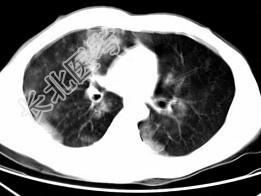

- 单项选择题男,28岁, 外伤后1小时行胸部CT如图,其最可能的诊断为 ( )

E、双肺挫伤